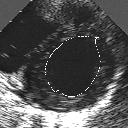

DETECTION AND TRACKING OF ANATOMICAL STRUCTURES USING DEFORMABLE TEMPLATES AND A NOISE MODEL ESTIMATION IN AN ECHOGRAPHIC SEQUENCE

In this work, we present a new method to shape-based segmentation of deformable anatomical structures in medical images and validate this approach by detecting and tracking the endocardial border in an echographic image sequence. To this end, a global prior knowledge of the endocardial contour is captured by a prototype template with a set of admissible deformations to take into account its inherent natural variability over time. In this approach, the data likelihood model rely on an accurate statistical modeling of the grey level distribution of each class present in the image. The parameters of this distribution mixture are given by a preliminary estimation step which takes into account the distribution shape of each class. Then the tracking problem is stated in a Bayesian framework where it ends up as an optimization problem. This one is then efficiently solved by a genetic algorithm combined with a steepest ascent procedure. This technique has been successfully applied on synthetic images and on a real echocardiographic image sequence. This method seems to be particularly well suited to handle ultrasound images with strong speckle noise on which edge information cannot be exploited. Finally, the local and global minimization procedure we propose is fast, robust and do not require initialization of the template close to the desired solution. Initialization may be defined at random, leading to segmentation and tracking procedure that are completely data driven. (slides)

Figure 1:   Tracking of the endocardial contour in a medical echographic sequence at different time frames during the cardiac cycle. From top left to bottom right : frame 1, 4, 6, 9, 12, 13, 18, 20, 27, 30, 35, 40, 41, 44, 46.